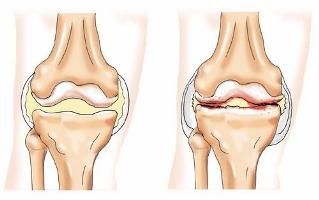

Você sabe o quanto as dores nas articulações podem tirar a liberdade do seu movimento — e se são especialmente incômodas na coluna, então se tornam limitantes: levantar-se, curvar-se, girar o corpo, até mesmo dar aquela espreguiçada no fim do dia podem virar fonte de desconforto constante. A coluna vertebral carrega não só o peso do corpo, mas também as tensões acumuladas ao longo do tempo — e quando as articulações ao redor dela começam a “rangê-las” ou travar, o impacto se espalha por toda a estrutura corporal.

Sulfato de condroitina: componente natural da cartilagem, que ajuda a preservar elasticidade e resistência — reduzindo o desgaste das articulações.

Colágeno tipo II (derivado de frango): específico para a cartilagem articular, auxilia na regeneração e manutenção da saúde articular.

Combate à inflamação, ao inchaço articular e à sensação de “travamento” que muitas pessoas sentem na região da coluna.

Porque ele não trata apenas o sintoma (a dor) — ele ataca a raiz da questão: desgaste da cartilagem, inflamação articular, comprometimento da estrutura que sustenta a coluna. Em vez de usar apenas analgésicos ou anti-inflamatórios que mascaram o problema, o Maxxi-Art 2.0 trabalha para regenerar, apoiar, fortalecer. Isso faz diferença sobretudo na coluna: quando suas articulações estão bem, a coluna inteira “respira” melhor — menos dor, mais movimento, mais liberdade.